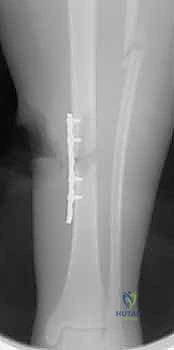

4. إدخال المسمار النخاعي والتثبيت النهائي

يتم تمرير مسمار التيتانيوم بدقة داخل العظم. وبمجرد التأكد من موضعه المثالي بالأشعة، يقوم البروفيسور هطيف بإدخال المسامير التشابكية (Locking Screws) العرضية في أعلى وأسفل المسمار لضمان التثبيت المطلق.

- التثبيت التشابكي (Interlocking): يتم تمرير مسامير صغيرة عرضية عبر العظم والمسمار النخاعي في الطرفين العلوي والسفلي، مما يمنع دوران العظم حول المسمار ويحافظ على طول الساق الطبيعي بدقة متناهية.